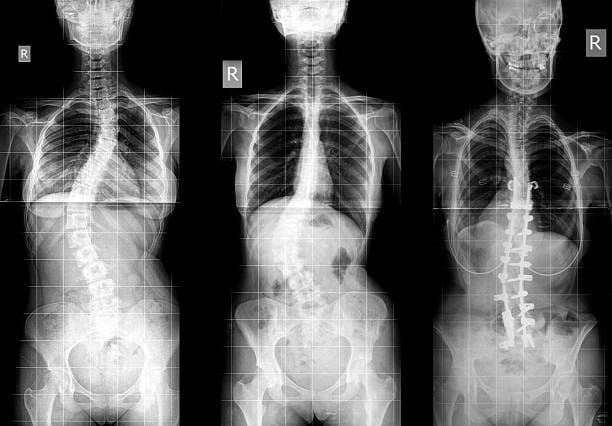

Scoliosis is a curvature of the spine that is often diagnosed in childhood. While most cases of scoliosis are mild and need very little or no treatment, some are more severe and require special therapies to correct. The therapy and treatment to correct scoliosis depend on the severity of the curve and other risk factors involved, such as the patient’s age, potential harm to organs, and the patient’s lifestyle.

While doctors aren’t certain what causes the most common types of scoliosis, it seems that genetic factors are involved, as it typically runs in families. Less common types—which are often more severe—are caused by birth defects, injuries or infections, or neuromuscular conditions like cerebral palsy, muscular dystrophy, or spina bifida. It has also been noted that girls tend to have a much higher chance of severe progression than boys.

- Curve pattern: an S-shaped curve tends to worsen over time much faster than a c-shaped curve

- Location of the curve: curves located in the thoracic area of the back progress more quickly than in cervical or lumbar regions